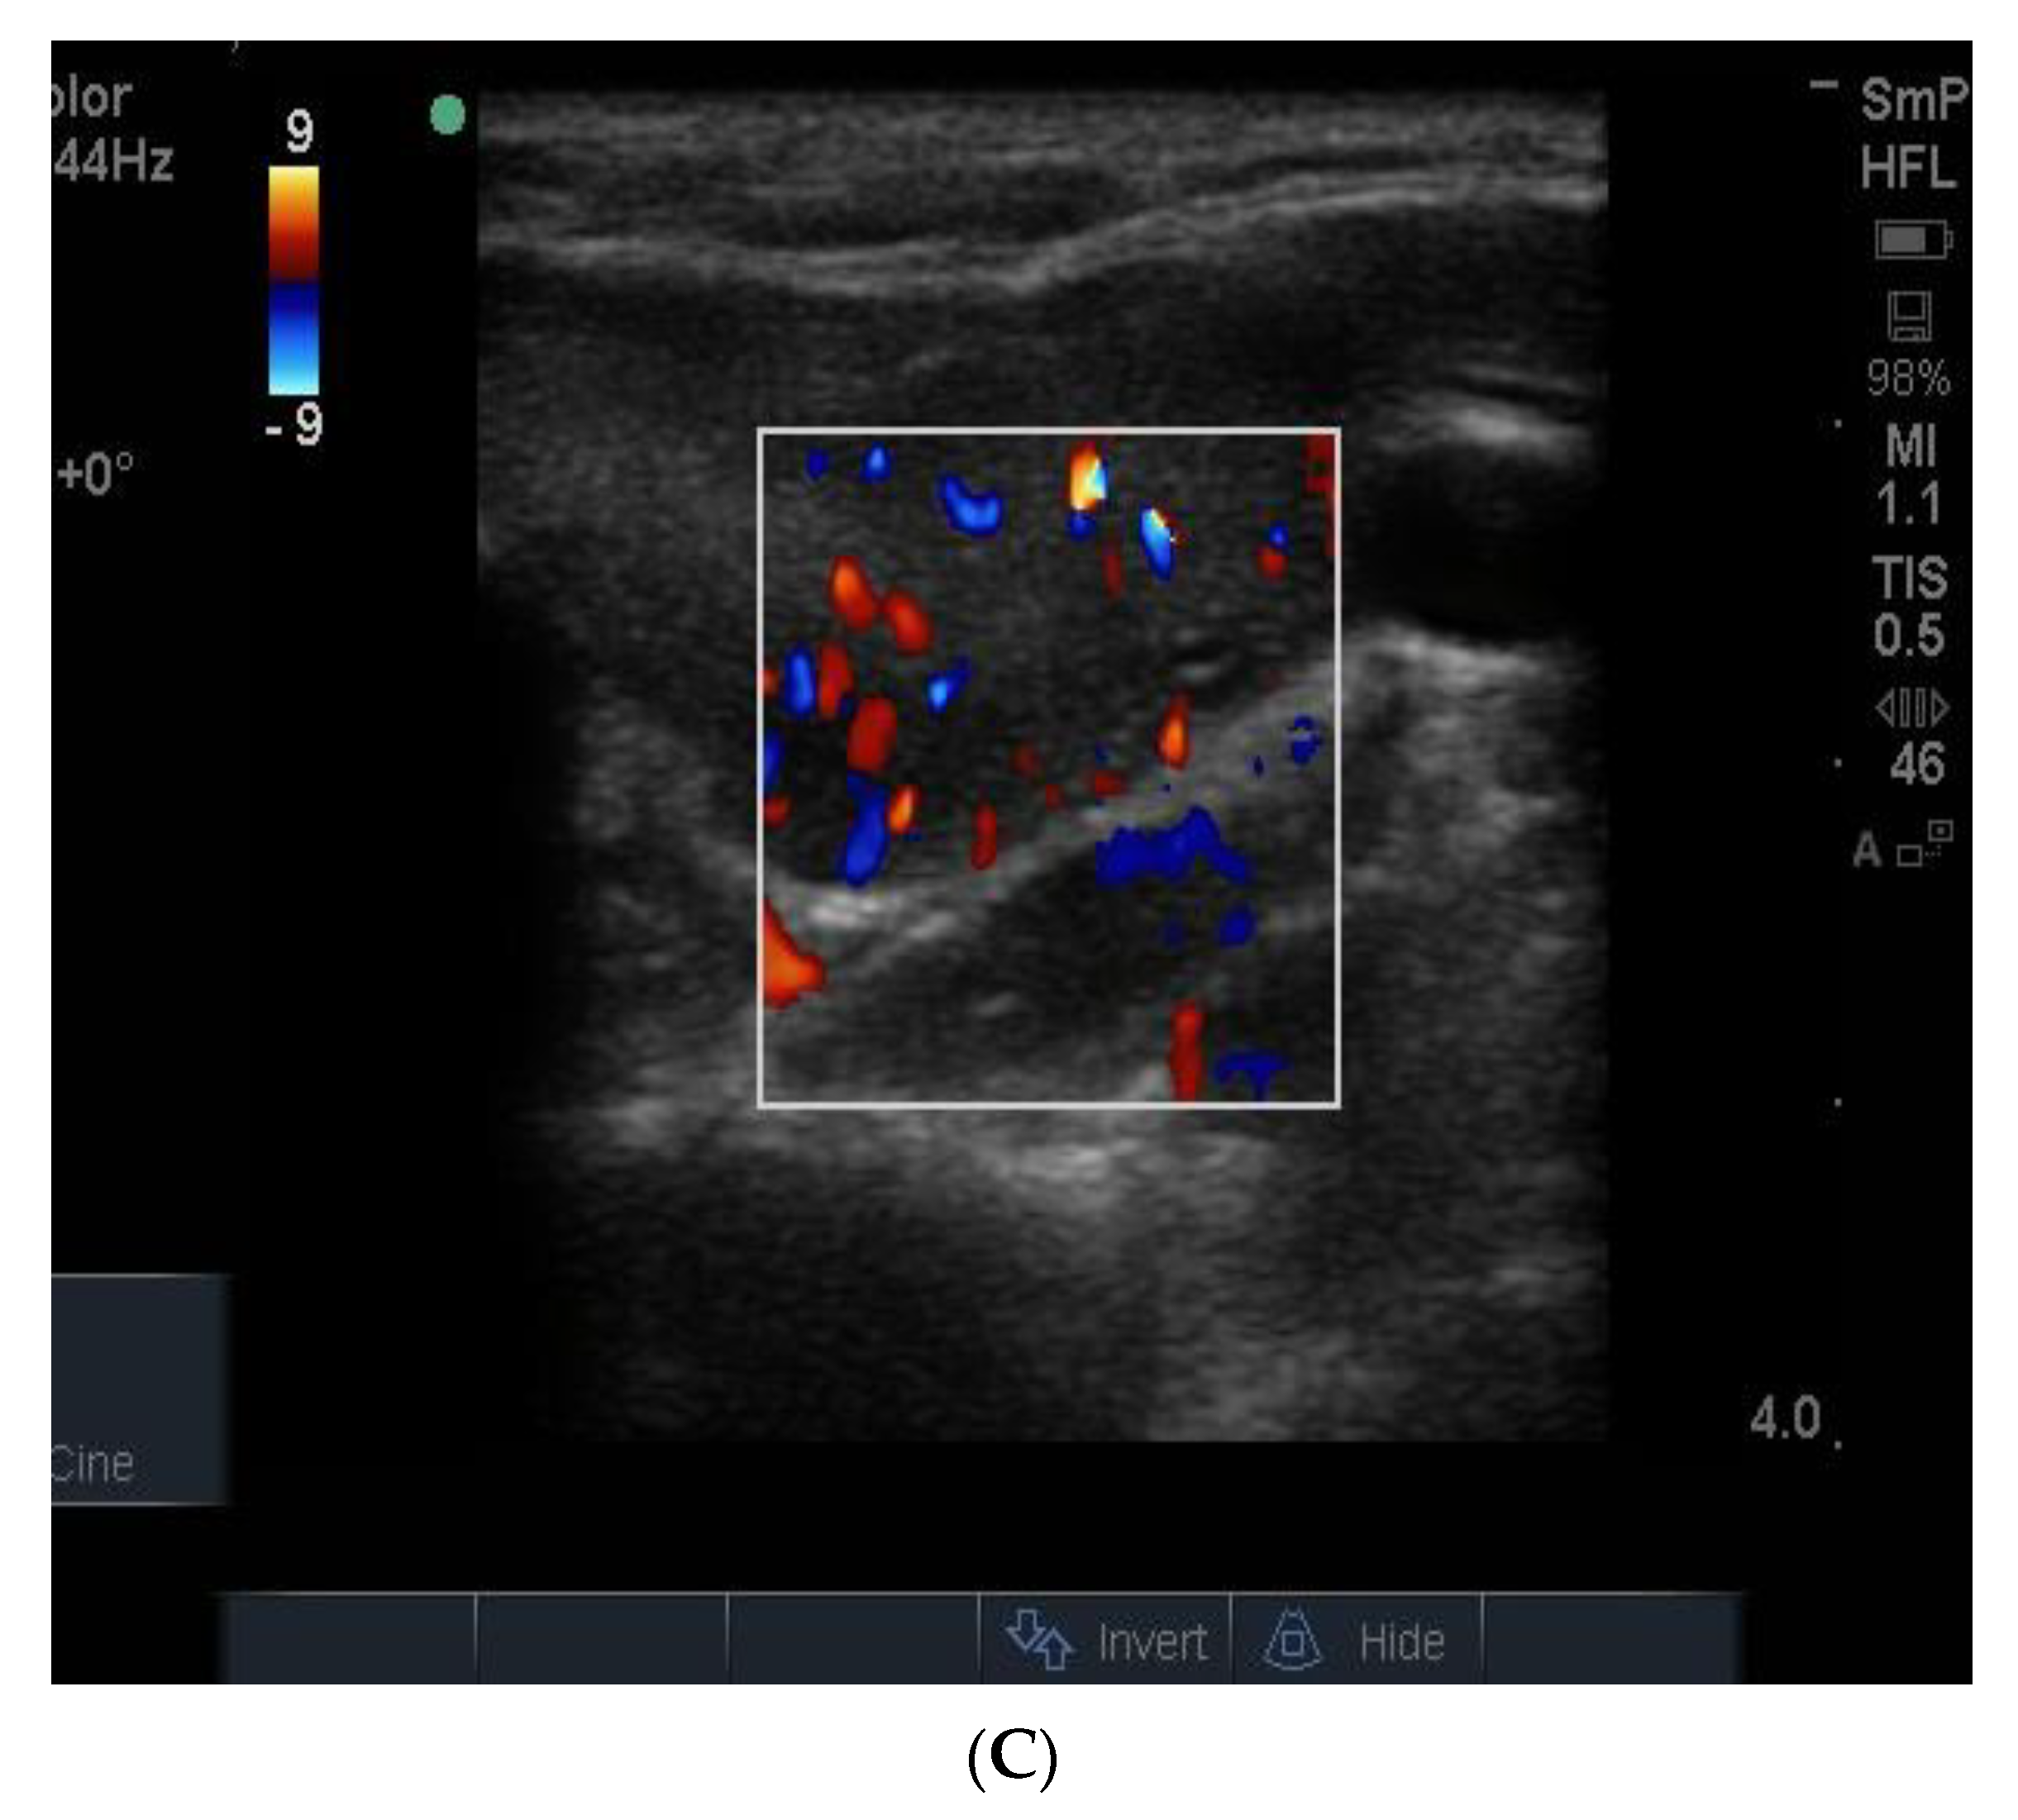

The blood supply in typical Graves’ disease is diffusely increased (and associated with a murmur), sometime up to 100 times normal, and the gland texture on ultrasound is usually heterogeneous (patchy) with a fine cystic appearance throughout, which reflects the diffuse nature of the inflammatory process (Figure 15). Following radio iodine treatment, the normal gland architecture is disrupted because the follicles are destroyed, and scar tissue predominates.

Figure 15. Thyroid ultrasound from two patients with Graves’ hyperthyroidism. In (A) is shown an example of early Graves’ hyperthyroidism manifest as multiple small inflammatory and lymphoid lesions, often described by the consultant radiologist as “nodules” blue arrow. In (B) is shown an enlarged thyroid, with a thick isthmus and a generalized patchy hypo echoicity due to the lymphocytic inflammation and thyroid cell proliferation. In (C) is shown the increased vascularity in the thyroid of the patient shown in (B).